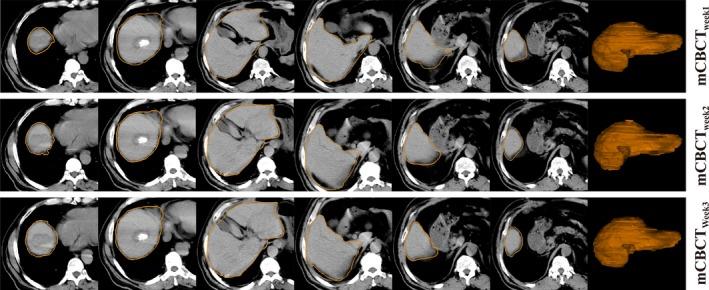

Many patients with technically unresectable or medically inoperable hepatocellular carcinoma (HCC) had hepatic anatomy variations as a result of interfraction deformation during fractionated radiotherapy. We conducted this retrospective study to investigate interfractional normal liver dosimetric consequences via reconstructing weekly dose in HCC patients. Twenty-three patients with HCC received conventional fractionated three-dimensional conformal radiation therapy (3DCRT) were enrolled in this retrospective investigation. Among them, seven patients had been diagnosed of radiation-induced liver disease (RILD) and the other 16 patients had good prognosis after treatment course. The cone-beam CT (CBCT) scans were acquired once weekly for each patient throughout the treatment, deformable image registration (DIR) of planning CT (pCT) and CBCT was performed to acquire modified CBCT (mCBCT), and the structural contours were propagated by the DIR. The same plan was applied to mCBCT to perform dose calculation. Weekly dose distribution was displayed on the pCT dose space and compared using dose difference, target coverage, and dose volume histograms. Statistical analysis was performed to identify the significant dosimetric variations. Among the 23 patients, the three weekly normal liver D increased by 0.2 Gy, 4.2 Gy, and 4.7 Gy, respectively, for patients with RILD, and 1.0 Gy, 2.7 Gy, and 3.1 Gy, respectively, for patients without RILD. Mean dose to the normal liver (D) increased by 0.5 Gy, 2.6 Gy, and 4.0 Gy, respectively, for patients with RILD, and 0.4 Gy, 3.1 Gy, and 3.4 Gy, respectively, for patients without RILD. Regarding patients with RILD, the average values of the third weekly D and D were both over hepatic radiation tolerance, while the values of patients without RILD were below. The dosimetric consequence showed that the liver dose between patients with and without RILD were different relative to the planned dose, and the RILD patients suffered from liver dose over hepatic radiation tolerance. Evaluation of routinely acquired CBCT images during radiation therapy provides biological information on the organs at risk, and dose estimation based on mCBCT could potentially form the basis for personalized response adaptive therapy.

许多技术上无法切除或医学上无法手术的肝细胞癌(HCC)患者在分次放疗期间因分次间变形而出现肝脏解剖结构变异。我们进行了这项回顾性研究,通过重建HCC患者的每周剂量来调查分次间正常肝脏的剂量学后果。23例接受常规分次三维适形放疗(3DCRT)的HCC患者纳入了这项回顾性研究。其中,7例患者被诊断为放射性肝病(RILD),另外16例患者治疗后预后良好。在整个治疗过程中,每周为每位患者进行一次锥束CT(CBCT)扫描,对计划CT(pCT)和CBCT进行可变形图像配准(DIR)以获取修正后的CBCT(mCBCT),并通过DIR传播结构轮廓。将相同的计划应用于mCBCT进行剂量计算。每周剂量分布显示在pCT剂量空间上,并使用剂量差异、靶区覆盖和剂量体积直方图进行比较。进行统计分析以确定显著的剂量学变异。在这23例患者中,有RILD的患者每周三次正常肝脏剂量分别增加0.2 Gy、4.2 Gy和4.7 Gy,无RILD的患者分别增加至1.0 Gy、2.7 Gy和3.1 Gy。有RILD的患者正常肝脏的平均剂量(D)分别增加0.5 Gy、2.6 Gy和4.0 Gy,无RILD的患者分别增加0.4 Gy、3.1 Gy和3.4 Gy。对于有RILD的患者,第三次每周D和D的平均值均超过肝脏放射耐受量,而无RILD的患者的值低于该耐受量。剂量学结果表明,有和无RILD的患者之间的肝脏剂量相对于计划剂量有所不同,且RILD患者的肝脏剂量超过肝脏放射耐受量。放疗期间对常规获取的CBCT图像进行评估可提供有关危及器官的生物学信息,基于mCBCT的剂量估计可能为个性化反应适应性治疗奠定基础。